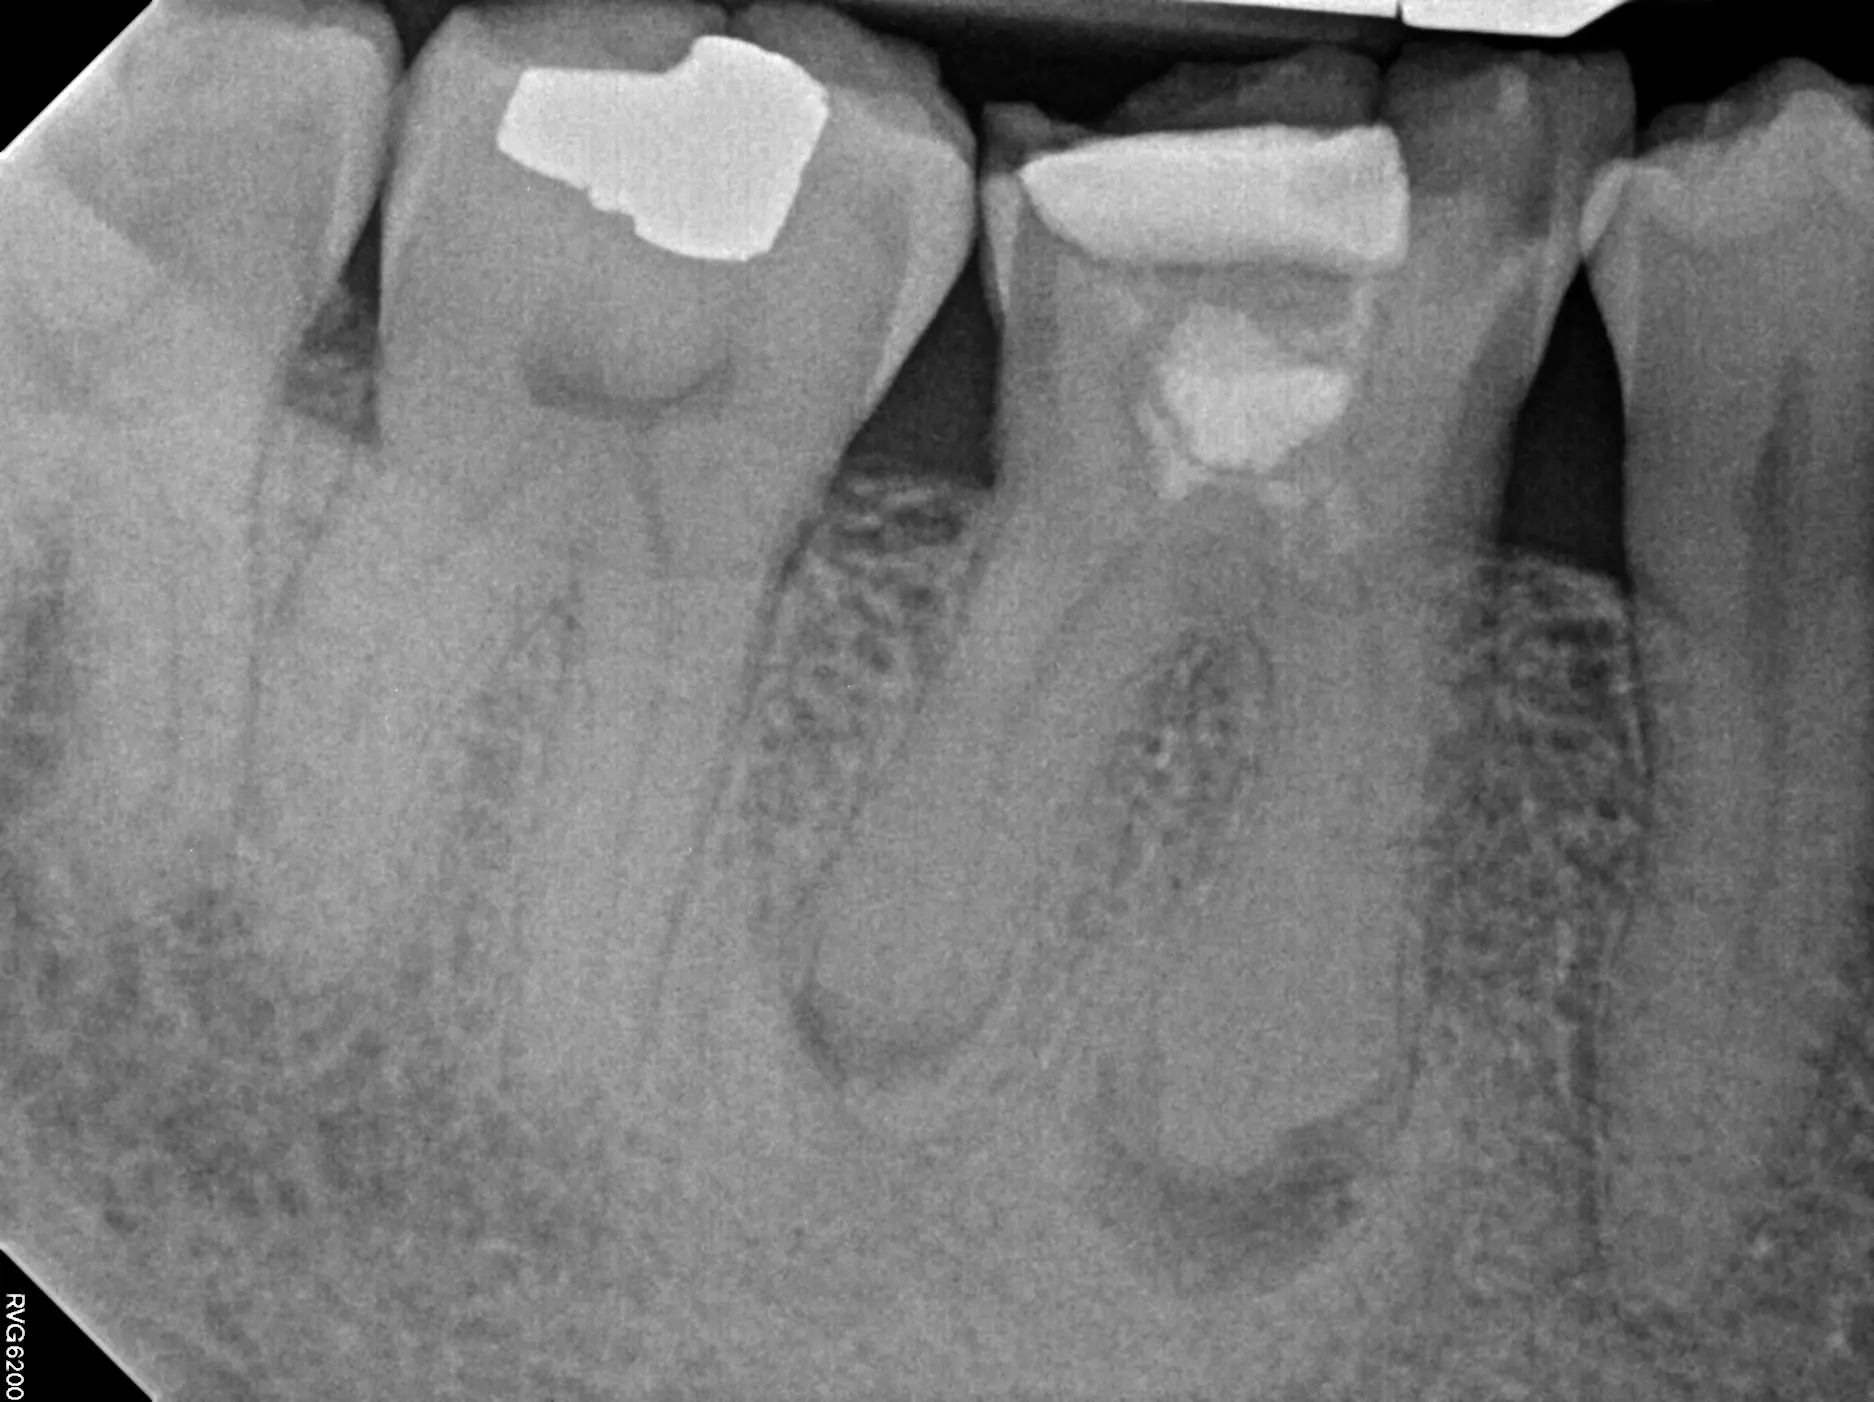

- Complicated canals were not detected during initial treatment.

- Curved or narrow canals weren’t treated.

New problems such as decay or a cracked or loose-fitting crown can also expose the tooth to new infection.

Retreatment involves the doctor reopening the tooth to gain access to the root canal filling material. The restorative material will be removed. The doctors will clean your canals and examine the problematic tooth. Once cleaned, the doctor will fill and seal the canals and place a temporary filling in the tooth.